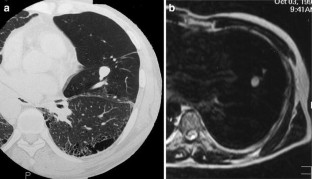

Congenital lung malformations (CLM) comprise a broad spectrum of maldevelopment that spans a continuum of maldevelopment involving parenchyma, bronchi, and vasculature. They may present as respiratory symptoms at birth and can be the source of morbidity and mortality. Early diagnosis is important for adequate therapy to prevent complications, such as recurrent infections, or to help normal lung development. Prenatal diagnosis of CLM using ultrasound (US) and magnetic resonance imaging (MRI) has increased, but chest radiography and computed tomography (CT) still play important roles in making diagnosis. This article reviews the clinical and radiographic features of various CLM.